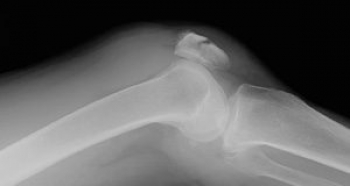

ɨ³¸¹ü¹üÀÞ¤ÎʬÎà

­¡²£¹üÀÞ

­¢½Ä¹üÀÞ

­£Ê´ºÕ¹üÀÞ

ɨ³¸¹ü¹üÀÞ¤ÎȯÀ¸µ¡½ø

ľã³°ÎÏ

žÅݤʤɤˤè¤êɨÁ°Êý¤ò¶¯ÂǤ·¡¢¹üÀÞ

²ðã³°ÎÏ

ÂçÂÜ»ÍÆ¬¶Ú¤Î¸£°ú¤Ë¤è¤ê¡¢¹üÀÞ